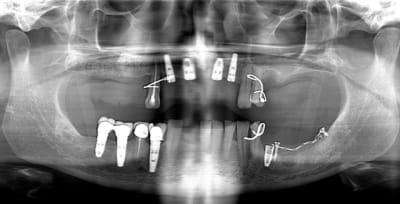

2 rétro-alvéolaire (septembre 2012)

un an après !

ça s'arrange pas, voyez plutôt..

augmentation de la perte osseuse +++